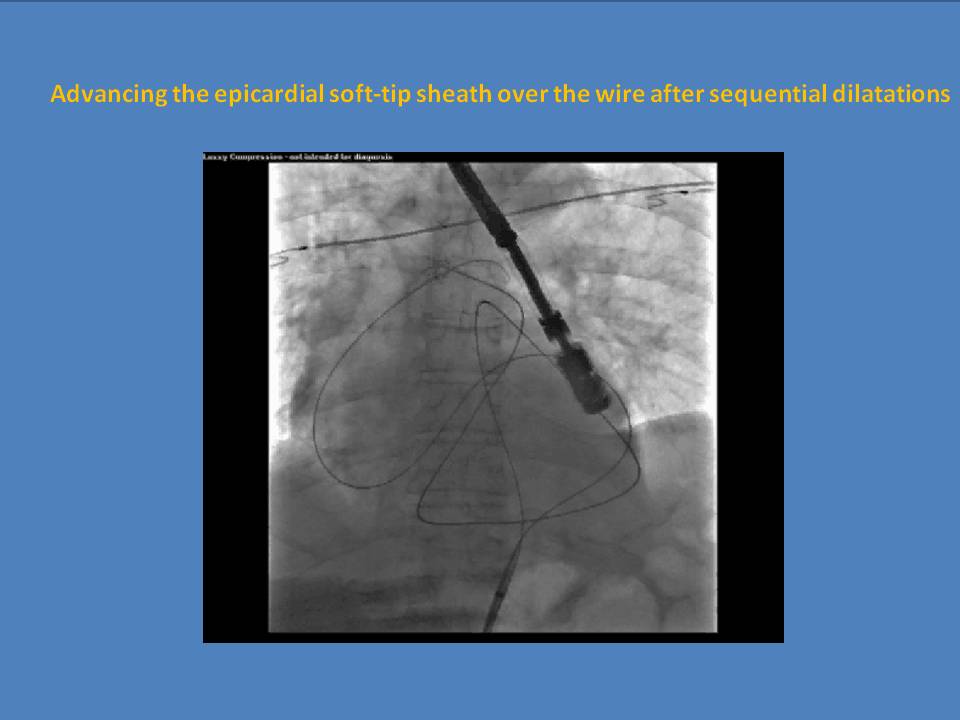

Percutaneous Left Atrial Appendage Ligation with Lariat